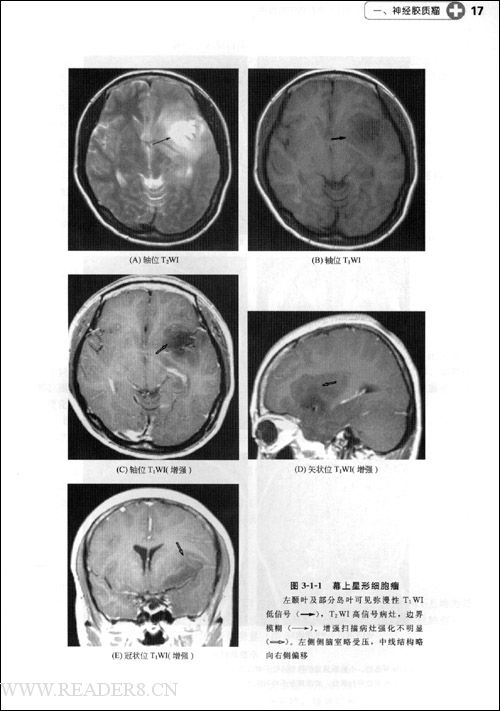

脑瘤手术及放化疗后的11种影像mri改变